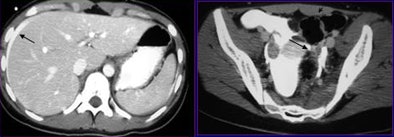

| A 52-year-old man after a motor vehicle collision. Initial axial CT scan (left) shows free fluid (arrow). This finding was suspicious for pancreatic injury. Five-minute delayed scan (right) demonstrates rupture of the upper pole of the left kidney associated with contrast material extravasation (arrow). The patient was treated conservatively. |